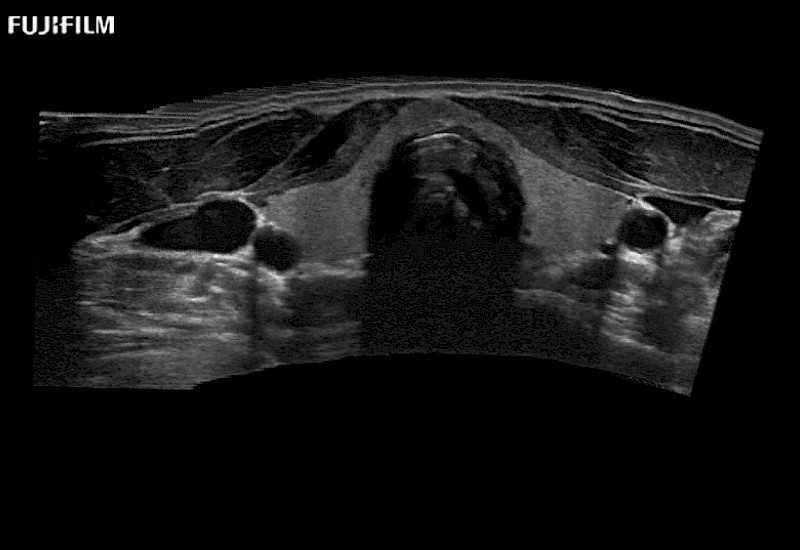

Curved array 4-way laparoscopic transducer for better visualization of targeted lesions.

Curved array “T” style finger-grip transducer for open surgical procedures.

Curved array deep penetration “I” style finger-grip transducer for open surgical procedures.